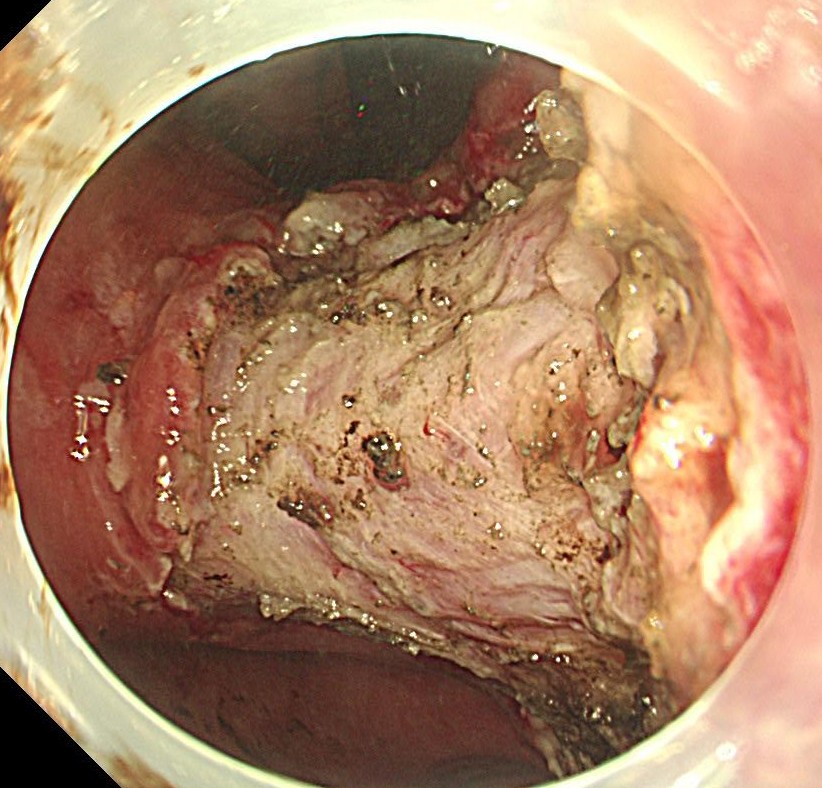

粘膜下層剥離術を開始します。粘膜下局注はこの症例は生理食塩水とムコアップを使用しました。

切除後の粘膜欠損部です。